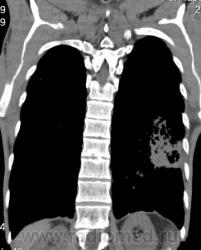

КТ - ОГК.  Ваше мнение коллеги?

На фоне консолидации полость без содержимого. Может быть всё что угодно, что сопровождается деструкцией. Нужны ещё томограммы в лёгочном окне.

Изображения выставлены все. Ваше мнение уважаемые коллеги?

Туберкулёз.

Туберкулёз?

Предположу аспергиллез